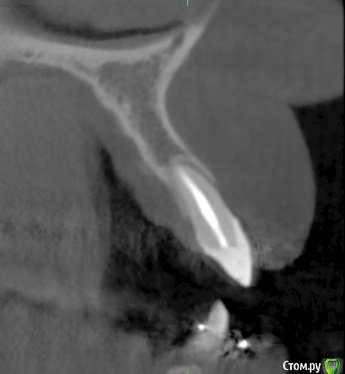

Zubik_Zubik Опубликовано 1 марта, 2019 Автор Поделиться Опубликовано 1 марта, 2019 (изменено) Как смог нарезал в кт. 1.Ортопед сказал что с небной подрезать нужно чутка.2.Насколько разумен такой вариант пока установлены брекеты. Спелить пломбу переклеить брекет с целью экструзии зуба, потом снова пломба и ретейнер. После небольшого отдыха нормальная коронка +3 винира 21, 11, 12. Спасибо Изменено 1 марта, 2019 пользователем Zubik_Zubik Ссылка на комментарий